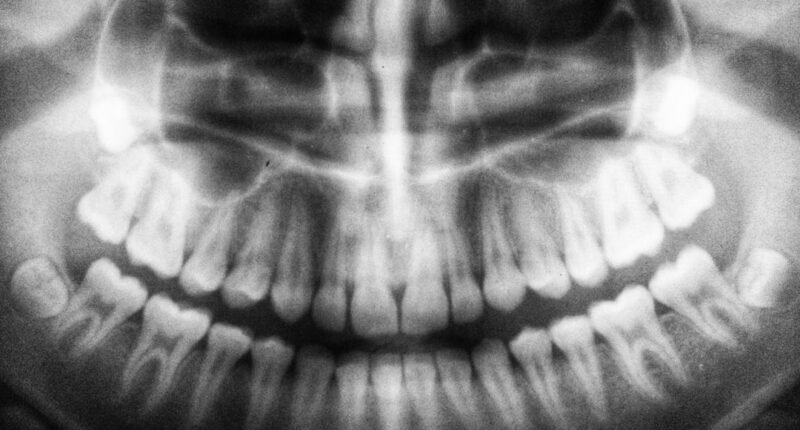

Monitoramento Global da Saúde Bucal

Organizações internacionais, como a OCDE (Organização para a Cooperação e Desenvolvimento Econômico), monitoram há décadas o desempenho de diversas nações em indicadores de saúde.

Esses relatórios nos ajudam a entender as tendências e os fatores que influenciam a qualidade dos sorrisos ao redor do globo.